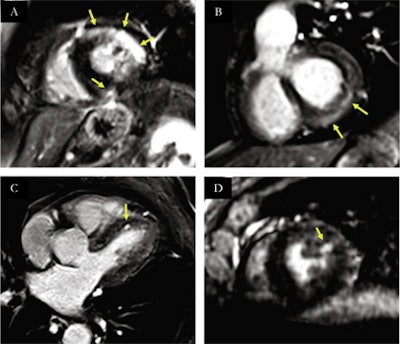

Spectrum of myocardial injuries on reformatted free-breathing high-resolution LGE after COVID-19 infection. Yellow arrows indicate areas with LGE. (A) intramural and subepicardial LGE on the anteriolateral and inferoseptal segments, consistent with myocarditis. (B) subepicardial LGE on inferobasal and infero-latero-basal segments, consistent with myocarditis. (C) focal subendocardial LGE on antero-septal segment consistent with micro-infarction. (D) focal subendocardial LGE on anterolateral segment consistent with microinfarction. Image courtesy of the European Journal of Radiology.Overall, a definite diagnosis using the new sequence was obtained in 15 out of 20 of the COVID-19 patients, including myocarditis in nine, multiple microinfarctions in two, myocardial infarction in two, and takotsubo cardiomyopathy in two.